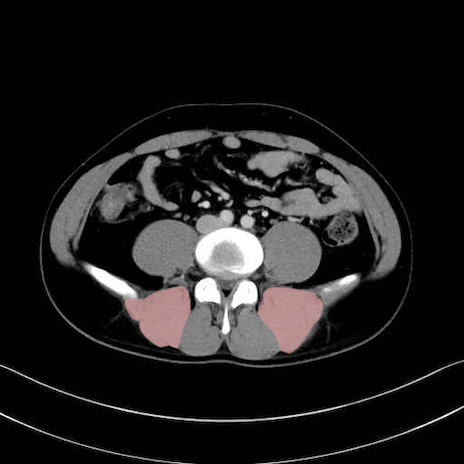

脊柱起立筋 (Erector spinae)

多裂筋 (Multifidus)